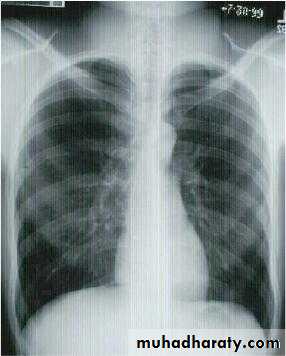

• A-Asymptomatic• Any smooth homogenous opacity of uniform density with clear cut border and little or no reaction around it on a chest X-Ray is a hydatid cyst unless proved the other wise .

• Radiological Findings

• 1-Smooth homogenous opacity (Intact H.C).• 2-Partial rupture (per vesicular pneumocyst).

• 3-Complete rupture (Water –lilly sign) .

• 4-Formation of lung abscess(Air –fluid level) .

• 5-Completely coughed out cyst(empty cavity )

• 6-Rupture into the pleura (hydropneumothorax)